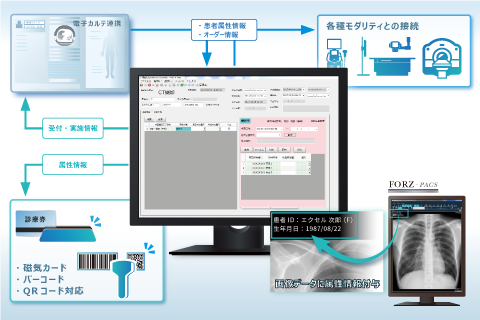

電子カルテ一体型ビューワ

電子カルテ一体型ビューワ マンモグラフィービューワ

MWM・RIS

MWM・RIS マッチングシステム